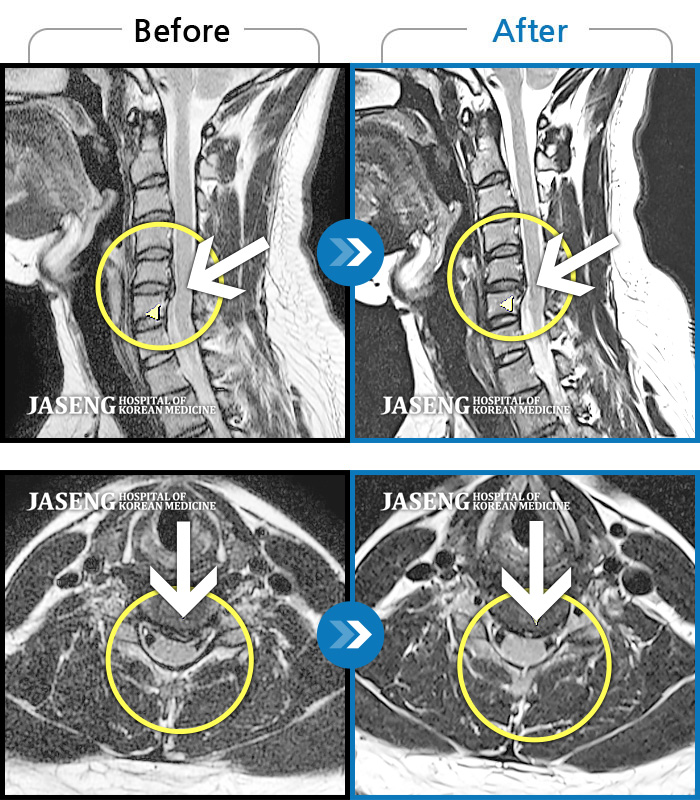

어깨와 목의 통증으로 1년여를 양방으로 치료하다 더해지는 불편감으로 장영우 원장님 진료를 받게 되었습니다. 원장님 치료를 받기 시작하면서 어깨는 물론 목의 뻐근함과 팔의 통증이 사라지고, 자유로운 일상생활 복귀로 너무 행복하고 감사한 마음이 가득입니다. 장영우 원장님의 진단과 침 치료는 정말 예리하고 완벽하신 것 같습니다. 친절하시고 마음도 따뜻한 장영우 원장님 너무 감사합니다.

교통사고를 당하여 입원 중 X-ray와 MRI촬영을 했었는데, 친절하게 사진을 보면서 진단결과를 상세히 알려주셨고, 그에 맞는 치료를 집중적으로 받게 도와 주셨습니다. 질문에도 상세히 응답해 주셔서 기분이 좋았습니다. 그래서 장영우 원장님을 칭찬합니다.

저는 60대 초반 주부입니다 21.4월경부터 손저림과 목 ㆍ등 통증 으로 신경외과 에서 MRI 한후 수술을 권유 받았지만 두려움으로 고민 하던중 지인의 소개로 자생을 알게되었습니다 ㆍ 무작정 상담 받은후 장영우원장님 께 진료를 하게되었습니다 첫인상 에 편안함과 신뢰할수 있는 말씀에 안심을 한후 입원치료를 하게 되었습니다 ㆍ 몇주동안은 별 차도가 보이지 않아 걱정도 되었지만 장영우원장님 말씀 믿고 치료받던중 3주가 지난후에 손저림은 완전 사라지고 목과 등 의 통증은 시간이 더 필요하단말씀 믿고 통원치료중입니다 ㆍ장영우 원장님의 따스한 위로 ㆍ의술 깊이 간직하고 살아가겠습니다 늘 건강하시길 기도 드리겠습니다 ㆍ

장영우 원장님! 환자의 마음을 편안하도록 웃으시며 치료하시는 모습에 감사드려요. MRi 판독을 자세하고 세부적으로 설명해주셔서 치료받는 제 몸상태에 대해 잘 알게 되었으며 추나치료도 정성껏 아픈부위를 정확하게 치료해주셔서 몸과 마음이 한결 부드러워졌습니다. 긴장하지 않도록 환자에게 여러가지 배려를 해주셔서 진료시간동안 웃으며 치료를 잘 받았네요. 건강한 몸을 위해 가정에서 쉽게 할 수 있는 운동을 자세하게 설명해주셔서 집으로 귀가 후 실행하였습니다. 꾸준한 관리로 다음 진료시간에는 건강한 모습으로 인사드리도록 하겠습니다. 장영우 원장님!! 무더위에 건강하시고 좋은 일들만 가득하세요. 감사합니다.^*^